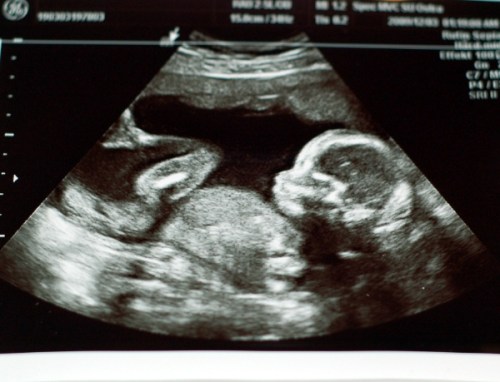

Vi hade varit riktigt snälla i år allihopa och tomten kom med fantastiska paket. Julmaten smakade riktigt gott och det var med dyster min jag insåg att jag inte skulle få i mig så mycket som jag önskat. Bebis tar upp mer och mer plats i magen för var dag som går och det hela känns mer verkligt än någonsin. Bilder säger mer än ord så här kommer lite bilder från vår jul.